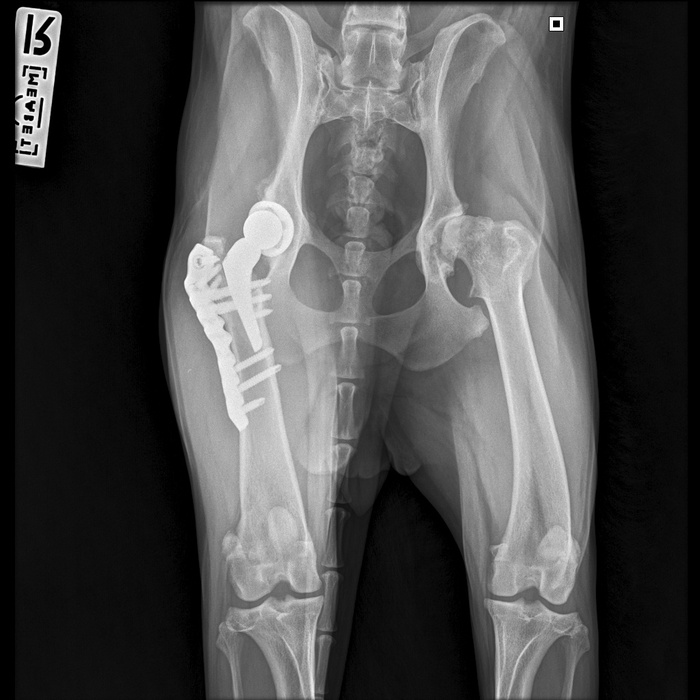

Вот как теперь выглядит ее внутренний мир